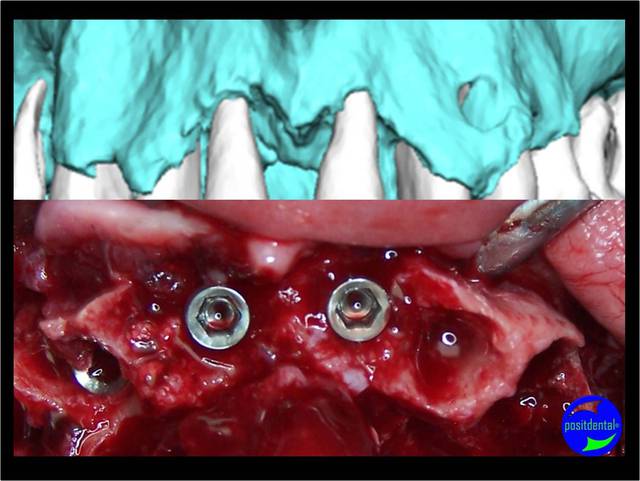

pour une mandibule

2h30 dtnqhc - Eugenol

A la mandibule :

Là pour lui , derrière il y a encore beaucoup de place , beaucoup d'os , enfin c'est un cas idéal ...)))